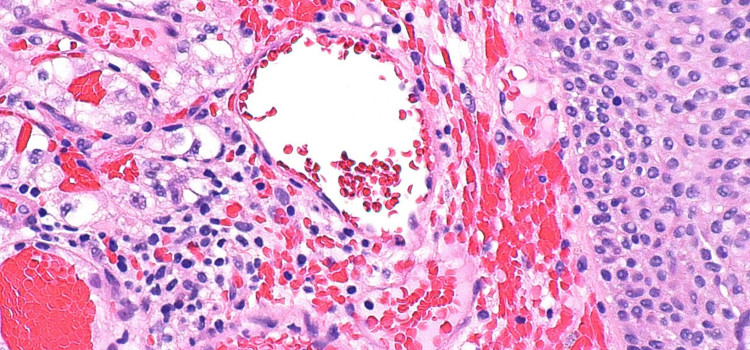

Hallazgo explica los efectos nocivos de algunos tratamientos contra el cáncer 11.03.2020 Los investigadores proponen un nuevo modelo de la estructura de los microtúbulos, que son esenciales en el funcionamiento de las células